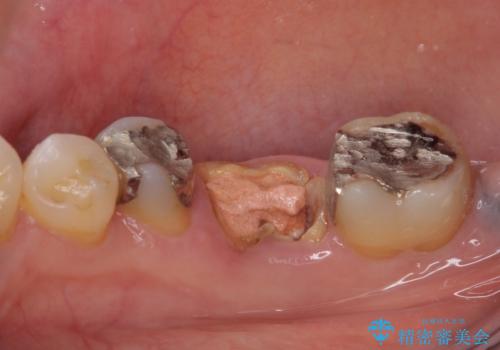

- 他院で、抜歯してインプラント補綴するしかないとのことで来院された患者様です。

診査したところ、抜歯と診断された歯は、他院での診断通り抜歯が必要でした。

ただし、インプラント以外にブリッジでの補綴治療も可能であったので、抜歯後に治癒を待って、フルジルコニアブリッジにて補綴することとしました。